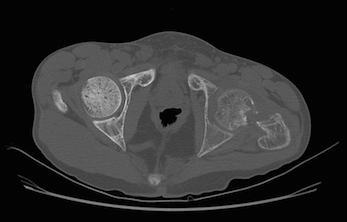

Alteração difusa do trabeculado ósseo em toda a região avaliada, associada a focos de reabsorção óssea subcondral na sínfise púbica e na borda anterior das sacroilíacas, relacionados à doença de base (hiperparatireoidismo).

Associam-se sinais de fratura patológica no colo do fêmur esquerdo, com reabsorção óssea junto ao foco de fratura e desalinhamento entre os fragmentos, com sinais de derrame articular do quadril homolateral, de aspecto reacional.